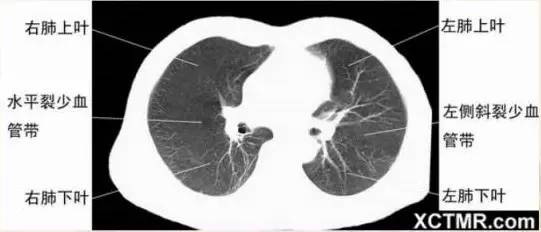

肺段划分